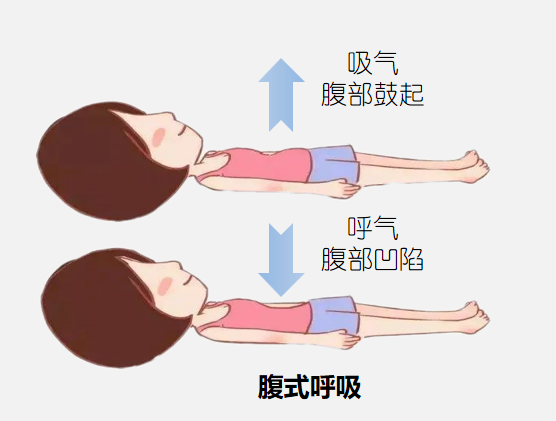

一项随机对照试验评估了(le)认知行为干预联合呼吸功(gōng)能训练在间质(zhì)性肺炎(yán)患者中(zhōng)的(de)应用效果,其中对照组在常(cháng)规护理基础上采用(yòng)呼吸功能(néng)训练,包含腹式呼吸、缩唇(chún)呼吸、阻力呼(hū)吸及(jí)相关呼(hū)吸训练(liàn),结果显(xiǎn)示,该治疗方式有效(xiào)增加了患者呼吸活动及膈肌活动(dòng)能力,使其肺容量增(zēng)加、氧气量更足,疾病症状改善(shàn)更好。

腹式呼吸:

取(qǔ)半坐(zuò)卧(wò)位(wèi),嘱患者全身放松并将双手放(fàng)置在腹部(bù),通过鼻子缓慢吸气(qì)训(xùn)练,双手位置不动(dòng),呼气时感受(shòu)腹部的手下降,每天(tiān)进行训(xùn)练,每组>20次。